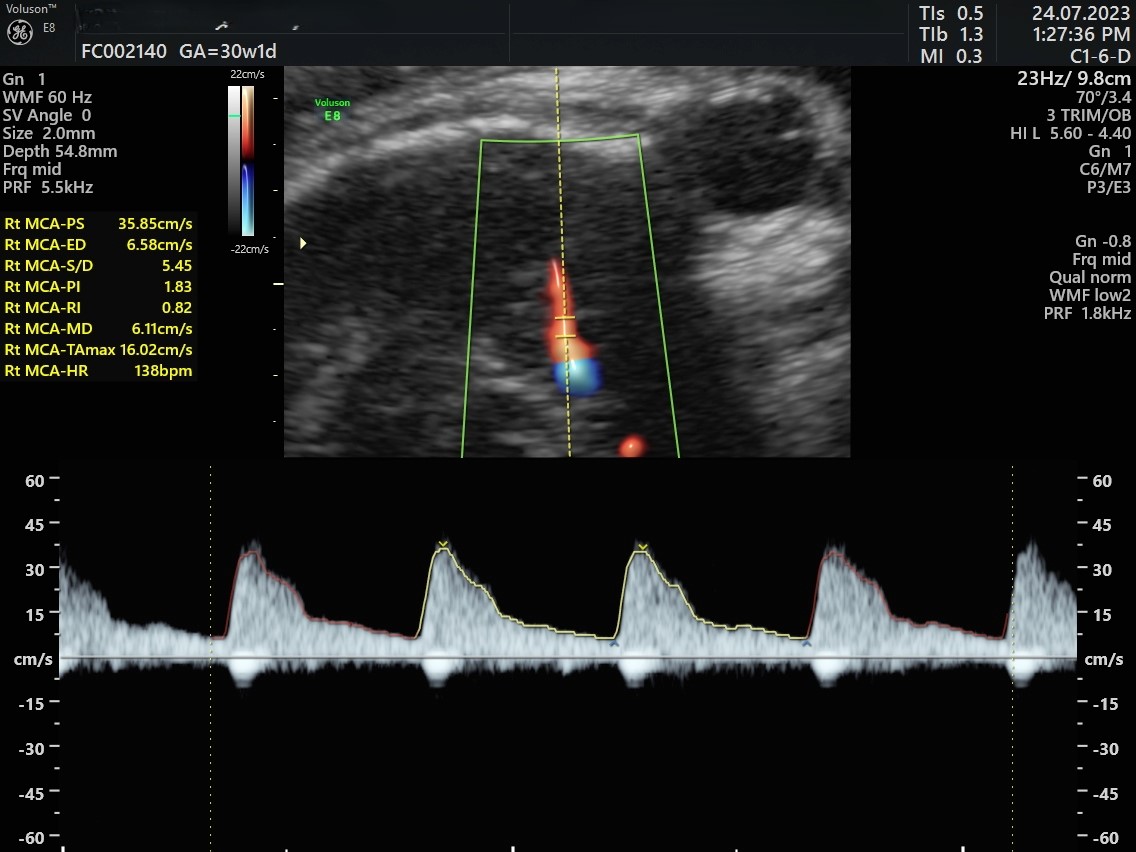

• Fetal Doppler study